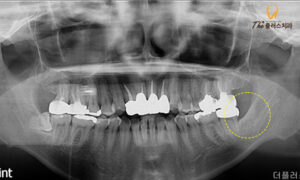

전체적으로 파노라마 사진을 통해

사랑니의 형태를 확인해 본 결과,

환자분께서 말씀해 주신 것처럼

아래 양옆으로 총 2개의 사랑니가

존재하였습니다.

둘 다 누워있는 형태이며 아래턱에

전반적으로 분포하는 신경관인

하치조 신경관과 중첩되어 있는

완전 매복치였습니다.

신경관과의 중첩을 자세히 확인해 보기 위해

3D CT 촬영을 진행하였고,